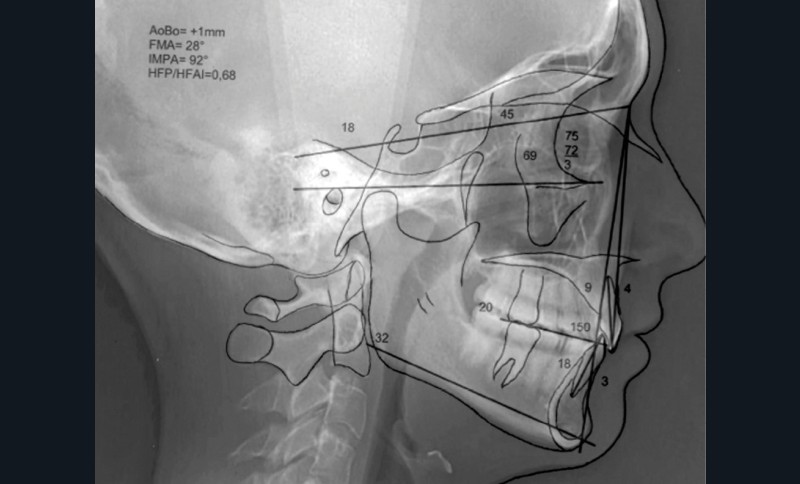

La radiographie panoramique et la téléradiographie de profil objectivent (fig. 3 et 4) :

- un espace rétro-molaire suffisant pour une distalisation ;

- des axes radiculaires molaires favorables à un redressement ;

- une classe I squelettique (angle ANB = 3°) ;

- une normodivergence (angle GoGn/SN = 32°)…